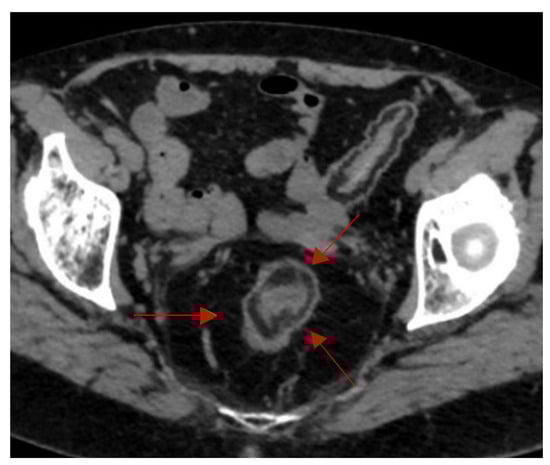

Abdomen and Pelvis

- Burkhardt, J.; Arshanskiy, Y.; Munson, J.; Scholz, F. Diagnosis of Inguinal Region Hernias with Axial CT: The Lateral Crescent Sign and Other Key Findings. Radiographics 2011, 31, E1–E12. [Google Scholar] [CrossRef]

- Hasbahceci, M.; Erol, C. Usefulness of Computed Tomography for Differentiation of Primary Inguinal Hernia. Gazi Med. J. 2015, 26, 170–173. [Google Scholar]

| Lateral Crescent | CT pelvis | Direct inguinal hernia | Specific for distinguishing direct vs. Indirect hernia | Helps guide surgical approach and repair strategy. |